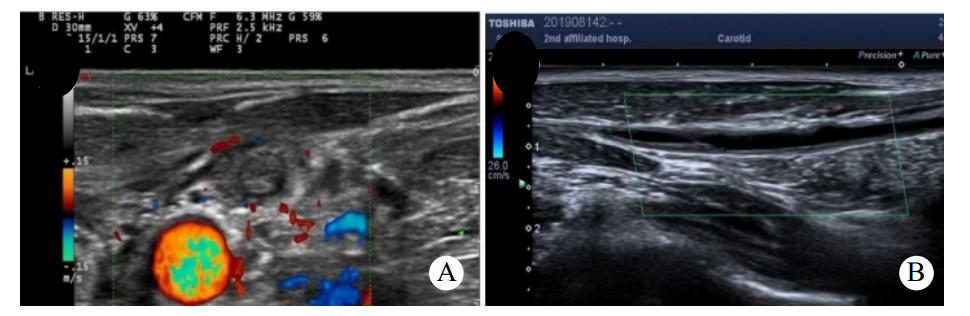

患者男,50岁,因“进行性左侧咽痛6 d”于2019年4月30日入院。患者6 d出现左侧牙痛、咽痛,伴发热(体温不详),未予治疗。3 d前咽痛加重,遂至当地医院就诊,CT提示左侧咽旁软组织肿胀伴喉腔变窄,超声提示左侧颌下腺炎,予以头孢米诺钠抗感染治疗后咽痛无好转,并出现呼吸困难及胸闷,左侧颈部肿痛。10 h前转入本院急诊就诊。否认糖尿病、高血压、吸烟、饮酒史。查体:双侧扁桃体无肿大充血,左侧咽侧壁肿胀,左侧颌下及颈部肿胀,压痛明显,局部皮肤红肿,皮温升高。血常规:白细胞计数7.2×109/L、中性粒细胞6.14×109/L、中性粒细胞百分比85.2%。C反应蛋白 > 270.0 mg/L。凝血谱:D-二聚体2960 μg/L、血浆纤维蛋白原10.98 g/L。颈胸部增强CT:左侧咽旁间隙、左侧颈部、中后纵膈脓肿形成,左侧颈内静脉血栓形成考虑,双侧胸腔积液。见图 1。拟诊为咽旁脓肿,纵膈脓肿,左侧颈内静脉血栓,胸腔积液。急诊行颈侧切开咽旁、颈部脓肿切排引流,纵膈胸膜切开排脓、胸腔脓肿清除、胸腔闭式引流。颈部留置引流管2根,食管后间隙留置胸管1根,右侧胸腔留置胸腔引流管1根。脓液送细菌培养和药敏检查。患者带气管插管入住ICU,予注射用亚胺培南西司他丁钠(泰能)0.5 g每6 h一次抗感染,那屈肝素钙注射液(速碧林)0.4 mL每12 h一次抗凝治疗,注射用甲泼尼龙琥珀酸钠(甲泼尼龙)40 mg每日3次抗炎,以及化痰、护胃、补液等对症支持治疗。术后第2天转入普通病房,细菌培养及药敏结果:咽峡炎链球菌,对当前使用抗生素敏感,未更改抗生素。术后2次血培养结果均为阴性。术后持续牙痛并有持续性低热,请口腔外科会诊,考虑牙源性感染,建议待感染控制后拔除病灶牙。术后白细胞总数逐渐增加,C反应蛋白及降钙素原逐渐下降。术后第9天,出现左侧颌下及颈部肿胀,压痛明显,局部皮肤红肿,皮温升高,急诊行颈部及胸部CT提示:咽旁、颈部、纵膈脓肿术后改变,左侧颈部软组织内及上纵隔积气。两肺背侧少许渗出,两侧少量胸腔积液伴部分肺组织膨胀不全,较前5月1日渗出有吸收,积液有增多,右侧叶间包裹性积液。考虑颈部引流不畅,急诊行颈侧切开颌下、咽旁、颈部脓肿切排引流,颈部重新放置2根引流管。术后白细胞总数开始下降。术后22 d出院,复查颈静脉超声(图 2A)提示左侧颈内静脉闭塞,出院后改用利伐沙班片20 mg口服每日3次,抗凝治疗3个月。术后4个月复查超声(图 2B),左侧颈内静脉部分再通。

| A:出院时,超声提示左侧颈内静脉闭塞;B:术后4个月,超声提示左侧颈内静脉血栓形成后改变,内径变窄,最窄处内径0.11 cm 图 2 出院与术后4个月左侧颈静脉超声 |